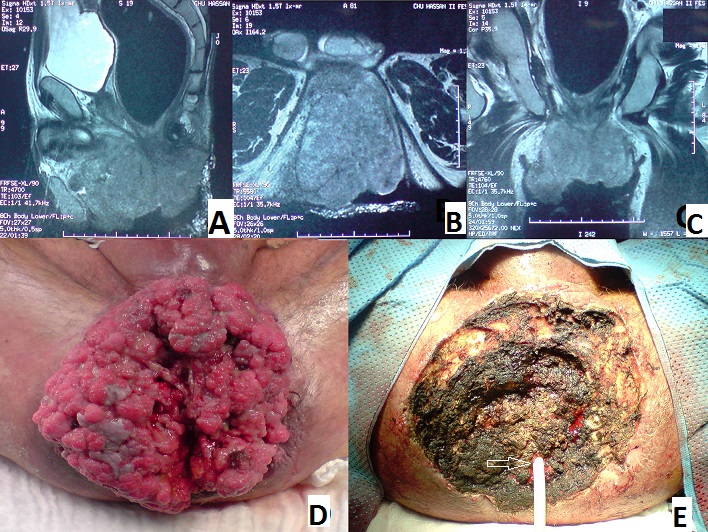

La tumeur de buschk loewenstein (TBL) ou condylome acuminé géant est une MST à papilloma virus humain, elle est rare est toujours précédée du condylome acuminé. Cette tumeur épithéliale se caractérise essentiellement par son taux important de récidive, par son potentielle de transformation maligne et par son extension en profondeur. Nous présentons un cas d'un patient âgé de 52 ans, sans antécédents pathologiques notables, qui présente une TBL à localisation anale évoluant depuis plusieurs années. Cliniquement c'est une énorme formation péri anale faisant environ 17 cm de grand axe, ulcéro-bourgeonnante, macérée, nauséabonde, saignant au contacte. Une biopsie à été réalisée et le caractère condylomateux viral avec absence de signe de malignité a été confirmé sur l'histologie. L'IRM pelvienne a objectivé une extension au canal anale, à la graisse pelvi-réctale et en avant vers la racine de la verge (A, B, C). Nous avons réalisé une exérèse tumorale par voie périnéale emportant la quasi-totalité de la tumeur épargnant le sphincter anal et arrivant jusqu'au planché périnéal (D,E), les suites opératoires étaient simple. L'étude anatomopathologique de la pièce ne retrouve pas de territoire d'invasion ou de dégénérescence.